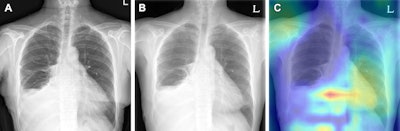

Пример сортировки без изменений на паре рентгенограмм грудной клетки в отделении неотложной помощи.  (А) На исходной задне-передней рентгенограмме грудной клетки у 63-летней пациентки выявлен небольшой объем левого (L) плеврального выпота и частичный ателектаз правой средней доли.  (B) Последующая рентгенограмма грудной клетки в задне-передней части, полученная у того же пациента через 1 день, не выявила существенных изменений.  (C) Карта активации градиентно-взвешенного класса показывает, что алгоритм не определил никаких изменений в паре изображений, без соответствующего выделения, поскольку выделенная область расположена над желудочно-пищеводным переходом.  Изображение предоставлено Радиологией.Пример сортировки без изменений на паре рентгенограмм грудной клетки в отделении неотложной помощи. (А) На исходной задне-передней рентгенограмме грудной клетки у 63-летней пациентки выявлен небольшой объем левого (L) плеврального выпота и частичный ателектаз правой средней доли. (B) Последующая рентгенограмма грудной клетки в задне-передней части, полученная у того же пациента через 1 день, не выявила существенных изменений. (C) Карта активации градиентно-взвешенного класса показывает, что алгоритм не определил никаких изменений в паре изображений, без соответствующего выделения, поскольку выделенная область расположена над желудочно-пищеводным переходом.